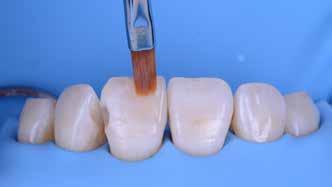

A módszer első lépéseként a gipszből kiöntött csonkokat platinafóliával borítjuk (5. ábra). Az adaptálását követően a felhelyezett fóliát óvatosan eltávolítjuk, felhevítjük, majd ismét visszahelyezzük a csonkokra. Ezt követően történik meg az első kerámiaréteg felvitele (Waschbrand). Az első égetés során csupán egy nagyon vékony réteg kerámia kerül a fólia felszínére (6. ábra). Amikor az égetést követően ezt

a kezdetleges kerámiavázat visszahelyezzük a csonkokra, a kerámia anyagában vékony repedések alakulnak ki. A végleges restaurátum elkészítéséhez szükséges kerámia „köpeny” ekkor áll készen a további kerámiarétegek felvitelére és kiégetésére (opaker réteg, dentin- és zománcmassza felvitele) (7-10. ábra). A készülő fogpótlás végső formai megjelenése rétegenként kerül kialakításra.